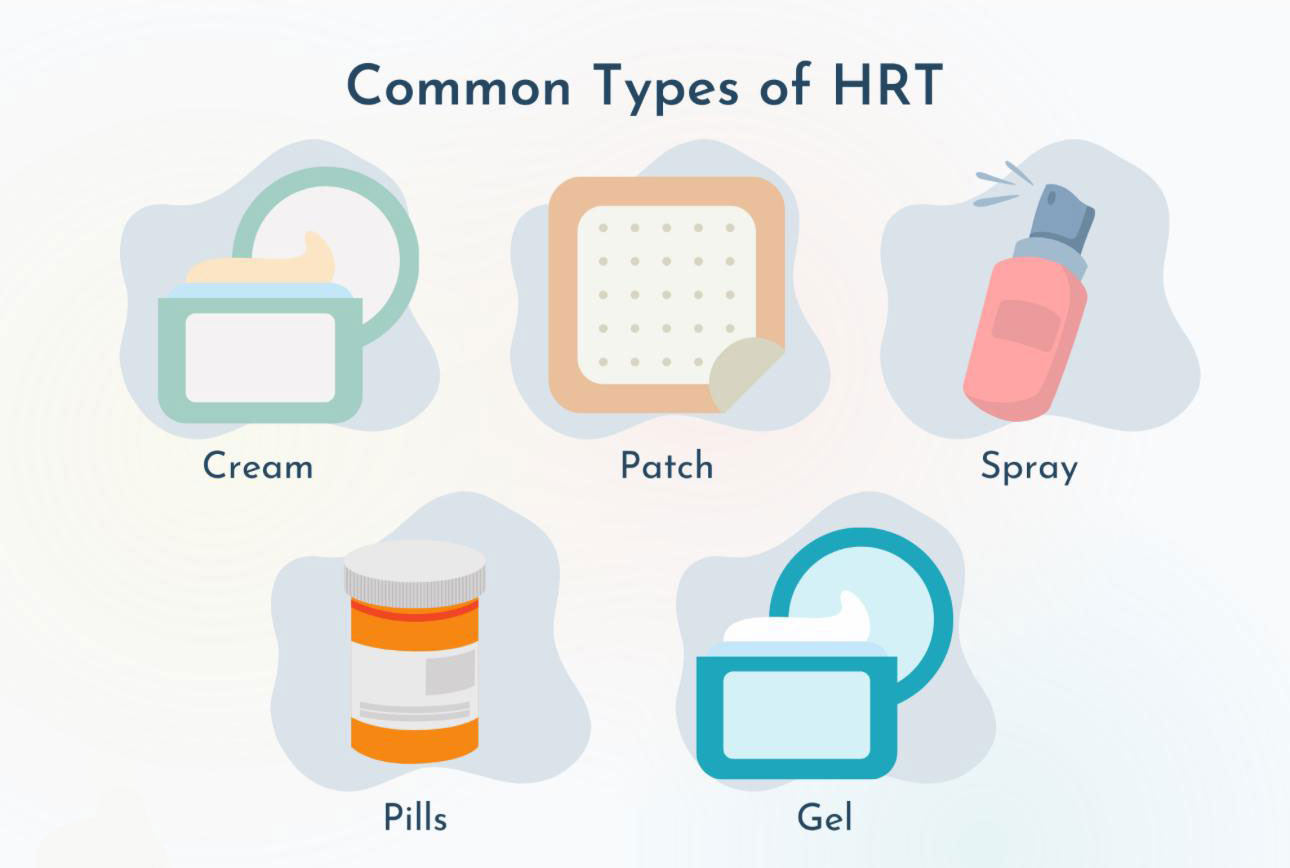

Hormonii estrogeni body-identical sunt hormoni produși în laborator, care au o structură moleculară identică cu estrogenii produși în mod natural de corpul uman. Acești hormoni sunt utilizați în terapia de substituție hormonală (HRT) pentru a trata simptomele menopauzei și alte afecțiuni hormonale, cum ar fi insuficiența ovariană prematură.